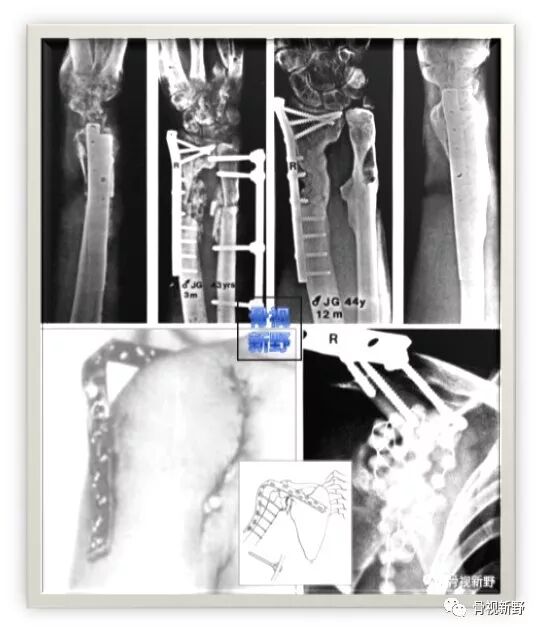

第三次报道:

2003年,Rene K.Marti团队再次报道了将AO标准钢板作为外固定架用于开放性骨折以及骨感染性骨不连的固定病例31例,也取得了较好的疗效。

锁定钢板的外固定应用

Cases